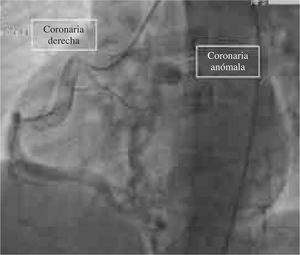

Caso clínicoPaciente varón de 21 años de edad que ingresa a nuestra unidad por el descubrimiento incidental de soplo continuo a nivel del foco pulmonar, además de disnea de moderados esfuerzos. Se inicia el estudio cardiovascular correspondiente con paraclínicos y gabinete propios al caso, obteniendo en la telerradiografía de tórax sólo un aumento considerable en el botón pulmonar del perfil izquierdo del corazón (Fig. 1). Al realizar el rastreo ecocardiográfico se identifica la ausencia de comunicación del tronco de la arteria coronaria izquierda al seno coronario correspondiente en la aorta, observándose un origen en el seno coronario izquierdo de la arteria pulmonar. La coronariografía confirma dilatación considerable de la arteria coronaria derecha, permitiendo ésta un llenado retrógrado del sistema arterial coronario izquierdo, el cual drena en la arteria pulmonar por un tronco anómalo de la coronaria izquierda (Fig. 2). Debido a la posibilidad de alteraciones en la perfusión cardíaca que se pueden presentar en las anomalías coronarias se realizó prueba de esfuerzo con protocolo de Bruce modificado, obteniendo cambios electrocardiográficos inespecíficos para isquemia.